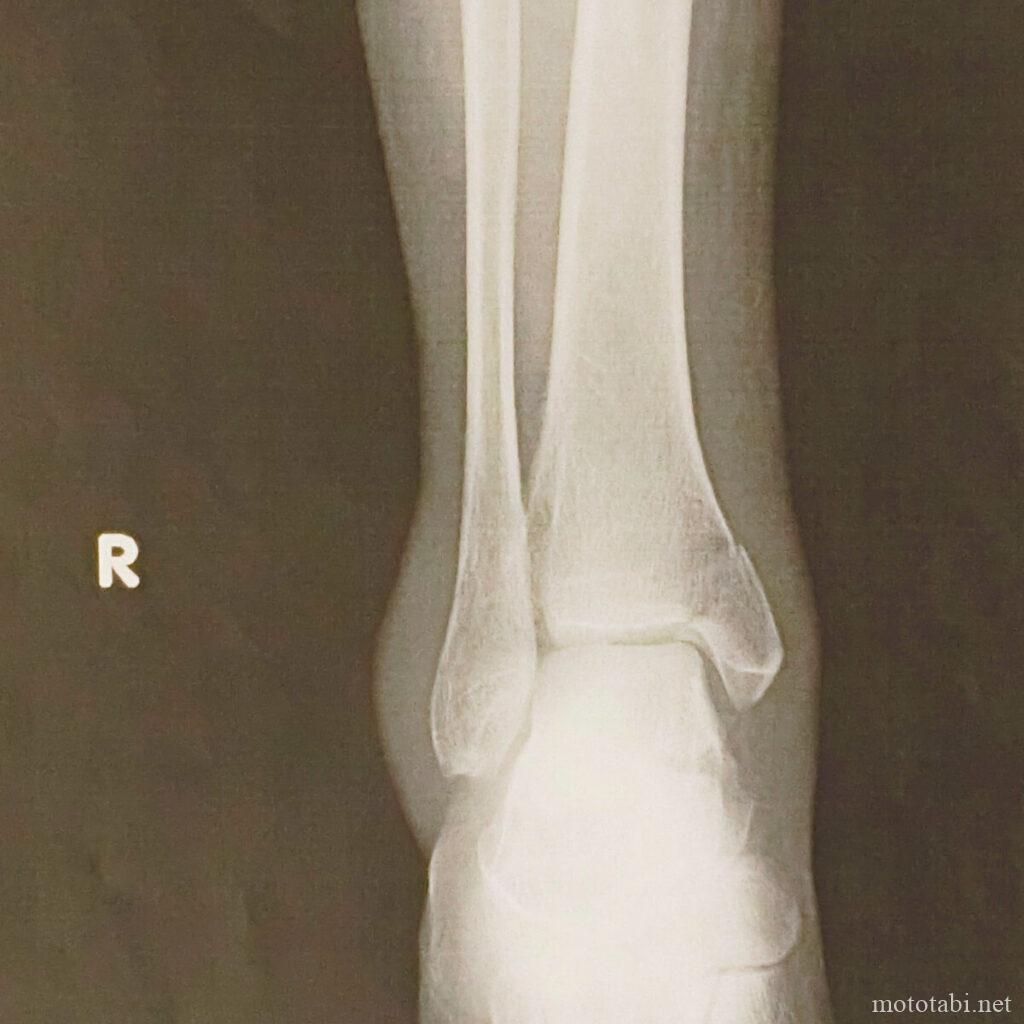

【骨折記録】半年、1年、1年半経過でどうなったか、ボルトは抜くのか骨折してから半年後、1年後、そして1年半後の記録です。 2019年9月、バイクで転倒...